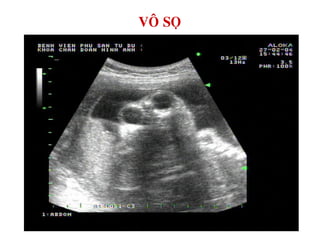

VOÂ SOÏ – LOÀI NAÕO

VOÂ SOÏ